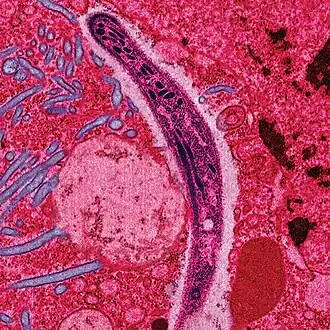

Le Plasmodium se présente sous la forme d'un protozoaire très petit (1 à 2 µm selon les formes). La coloration au May-Grünwald-Giemsa montre qu'il est constitué d'un cytoplasme bleu pâle entourant une vacuole nutritive claire et contenant un noyau rouge et du pigment brun-doré ou noir (hémozoïne).

Une première transformation arrondit cette forme « cryptozoïte » (du grec κρυπτός / kruptós, « caché ») en un élément uninucléé (avec un seul noyau) appelé trophozoïte qui est l'occasion pour le parasite de se multiplier directement (il en est toujours ainsi pour P. falciparum), par schizogonie, pendant une semaine à quinze jours aboutissant à un énorme schizonte (nom donné au protozoaire lorsqu'il devient actif après la phase d'incubation) de 40 à 80 μm. Ce corps bleu (parce que constitué d'un cytoplasme bleu pâle lorsqu'il est coloré au May-Grünwald-Giemsa) bourgeonne, tout en perdant de sa mobilité, de manière à émettre des vésicules, contenant les jeunes mérozoïtes qui seront transférés dans le sang, initiant ainsi le stade érythrocytaire, c'est-à-dire l'infection des globules rouges.